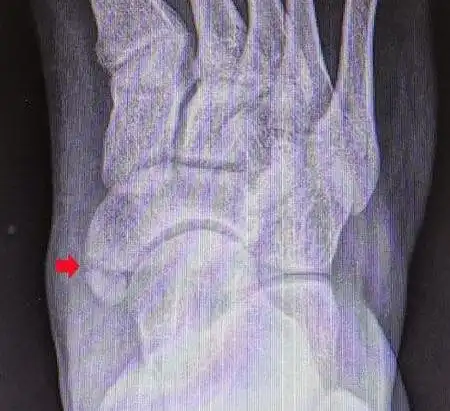

足内侧突出(副舟骨损伤)_踝部扭伤_症状表现_检查_治疗方式 - 好大夫